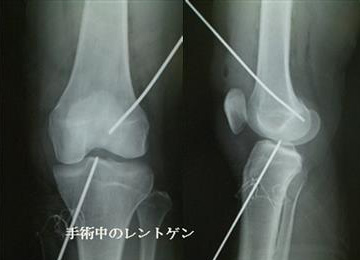

自分の組織を用いて再建する(自家腱移植)のがベストな方法とされています。当院で行っている膝屈筋腱(ハムストリングス)を用いた関節鏡視下膝前十字靱帯再建術は、切開は最小限で大きな合併症がなく、術後の成績も安定しているため、有効な治療方法として確立されています。 手術は膝関節を構成する大腿骨と脛骨の最適部位に関節鏡を用いて細いトンネルを作製し、そこに採取加工した腱を貫いて上端と下端を金具で固定することで膝の安定性を得ることを目的とし、全身麻酔+硬膜外持続麻酔下で行います。尚、本院では遺残靱帯(レムナント)が残存している患者様に対しては再生医療の観点※からレムナントを切除せずレムナントを利用し一重束前十字靱帯再建術(レムナント温存法)を、また女性で膝が柔らかい患者様(反張膝の患者様)などには二重束前十字靱帯再建術を、また二度目の受傷の患者様などには膝蓋腱を用いて一重束前十字靱帯再建術(BTB法)をおこなっています。また、縫合可能な半月板損傷がある患者様に対しては全例半月板縫合を行います。(Biomet MaxFire™ を利用し、関節内だけの操作で縫合します。)手術時間はレムナント温存法で行った時は約1時間から1時間半です。